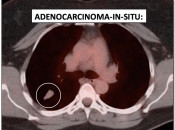

While PET/CT is sensitive for detecting most cancers, there are some malignancies which sometimes demonstrate poor avidity for 18F-FDG, including: [Fig. 1]

- Hepatocellular carcinomas

- Mucinous adenocarcinomas

- Neuroendocrine tumors

- Lobular breast cancers

- Adenocarcinoma-in-situ (formerly “bronchoalveolar carcinoma”)

- Renal cell carcinoma

- Prostate cancer

- Indolent lymphomas

Please note that while the above cancers sometimes demonstrate poor metabolic activity, they can also be quite FDG-avid. [Fig. 2]